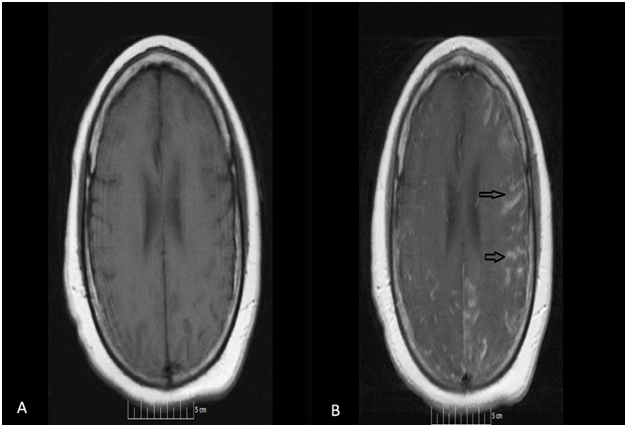

52-year-old African American female presented to our facility with altered mental status. Her past medical history was significant for Neurosarcoidosis, Diabetes Mellitus, Epilepsy and Hypertension. She was febrile with a temperature of 101.6F and mildly tachycardic to 103 beats per minute. Neurological examination revealed a divergent strabismus, a nonreactive right pupil, with no nuchal rigidity. Serum hematology and biochemistry was non-contributory. Urinalysis showed pyuria and bacteriuria. Chest x-ray showed increased interstitial markings prominent in the perihilar regions. Magnetic resonance imaging(MRI) of the brain with gadolinium showed post contrast diffuse leptomeningeal enhancement on T1 images (Figure 1, panel A & B), and there was a nodular pattern of leptomeningeal enhancement consistent with acute neurosarcoidosis (Figure 2). Lumbar puncture was unsuccessful due to body habitus. A preliminary diagnosis of urinary tract infection was formulated and broad spectrum antibiotics were instituted. Corticosteroids could not be administered as the patient was in severe sepsis.

Figure 2 MRI of the brain, T1 weighted with gadolinium contrast showing a nodular pattern of leptomeningeal enhancement consistent with acute neurosarcoidosis.